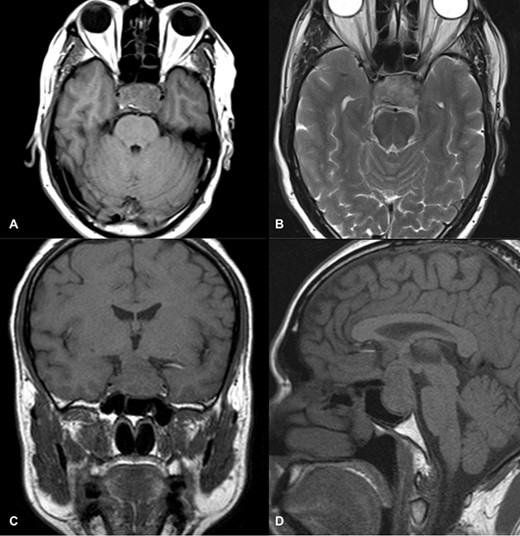

Magnetic resonance imaging (MRI) (axial T1, axial T2, coronal T1 and sagittal T1-weighted images) revealed a sellar and suprasellar lesion measuring 3 × 2.9 × 1.8 cm with patchy areas of high signal on T1-weighted images and signal void on T2-weighted images suggestive of hemorrhage. The suprasellar component of the lesion was displacing optic chiasma superiorly and the sellar component was causing sellar expansion with mass effect on bilateral cavernous sinuses (left>right); right internal carotid artery (ICA) had a contact angle of 90°, whereas left ICA had >90° (Fig. 1).

MRI images of axial T1 (A), axial T2 (B), coronal T1 (C), and sagittal T1-weighted images (D) showing a 3 cm × 2.9 cm × 1.8 cm sized suprasellar lesion displacing optic chiasma superiorly and laterally causing a mass effect on bilateral cavernous sinuses (Left>Right) with patchy areas of high signal on T1-weighted images and signal void on T2-weighted images suggestive of hemorrhage.